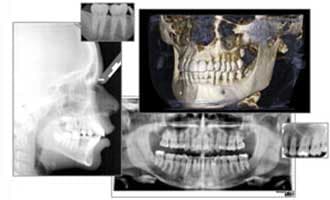

A Case Study of Acute Changes in Dental Occlusion: Digital CBCT Analysis

By DeWitt C. Wilkerson D.M.D. Fortunately, new advances in diagnostic imaging, such as Digital Cone Beam 3-D Technology, make it virtually impossible for pathology to escape diagnosis. To illustrate, let’s explore a challenging case to diagnose, beautifully exposed by digital CBCT technology. A 62-year-old Caucasian female presented with a chief complaint of progressive bite changes. Previously, all her teeth touched uniformly, but over the past 18 months this had gradually changed. The result was an open bite that extended from teeth #2–13, and a facial asymmetry with the mandibular plane of occlusion visibly canted significantly downward on the right side. She reported no pain; the left TM Joint felt normal